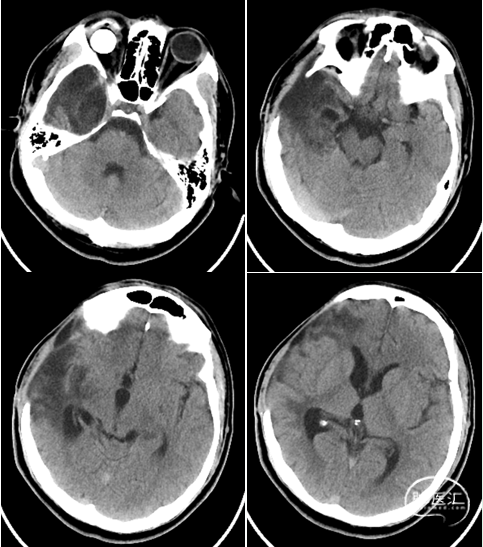

入院时影像

急诊颅脑CT+三维重建:

颅脑锐器损伤并异物存留,异物由右侧眼眶刺入颅内;右侧额颞叶挫裂伤并血肿形成;蛛网膜下腔出血;脑室系统较多积血;右侧额颞顶部少量硬膜下积血